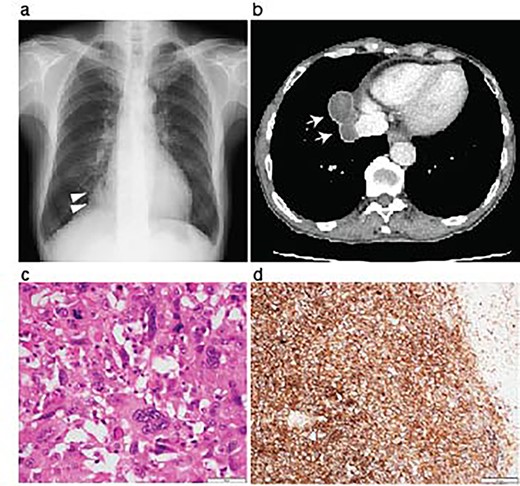

A 70-year-old man was referred to us for investigating an abnormal shadow in the right lower lung lobe in a computed tomography (CT) scanning. He had diabetes mellitus and an old myocardial infarction. The laboratory test of the patient showed slight anemia (Hemoglobin 11 mg/dL and red blood cell count 3.44×106/μL) without any coagulopathy. The patient also showed fecal occult blood. The preoperative colonoscopic examination revealed adenomatous polyps and a diverticulum in the descending colon that were considered the cause of fecal occult blood at that time. Tumor markers were as follows; Carcinoembryonic antigen 4.3 ng/ml, Neuron-specific enolase 7.2 ng/ml, Squamous cell carcinoma antigen 1.0 ng/ml and Pro-gastrin-releasing peptide 16.4 ng/ml. The chest X-ray showed a nodule in the right lower lung area (Fig. 1a). The chest computed tomography revealed a tumor in the right lower lobe, which was well-circumvented, 5.9 centimeters in diameter, and adjacent to the diaphragm and the inferior vena cava (Fig. 1b). The patient underwent a curative right lower lobectomy and mediastinal lymph node dissection with combined resection of the pericardium and diaphragm. The defect was reconstructed by suturing Gore-Tex™ sheet. The histological diagnosis of the tumor was pleomorphic carcinoma. The pathological stage was pT3N0M0, pStage IIB, as the tumor involved the pericardium. The patient was discharged on postoperative Day 10. Programmed death-ligand 1 (PD-L1) expression was >50% with immunohistochemistry (Fig. 1d). Being the pathological stage IIB, adjuvant chemotherapy with cisplatin and vinorelbine was indicated. The first dose was administered a month after the primary operation; however, the patient showed grade 4 leucopenia and nausea. The adjuvant chemotherapy was therefore discontinued.

Resection of the lung pleomorphic carcinoma. A chest X-ray on admission showed a nodule in the right lung field (arrowheads) (a). Enhanced CT-scanning showed a well-circumvented nodule along the inferior vena cava (b, arrows). Hemotoxylin and eosin staining of the resected tumor showed the mixture of spindle and giant malignant cells consistent with the pleomorphic carcinoma (c). Immunohistochemistry revealed high PD-L1 expression with a tumor proportion score > 50%. Scale bar, 50 μm (c), and 200 μm (d).

Interestingly, previous observational studies demonstrated that the non small cell lung carcinoma, including pleomorphic carcinoma that caused intestinal metastasis presented prominent PD-L1 expression [9, 10]. The PD-L1 expression of the lung tumor in this case was also high (Fig. 1d), and the patient responded to Pembrolizumab for the treatment of metastatic peritoneal lesions. The surgeries for the primary lung tumor and subsequent abdominal metastatic lesions were necessary to achieve the local tumor management and might have helped the patient to be able to undergo ICI treatment in good performance status.